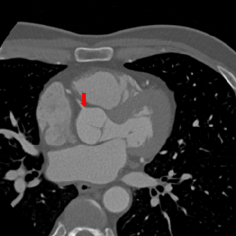

Figure 2: Axial slices from a CCTA scan, resized to an isotropic voxel size of 1.5 mm, in which reference landmark locations are indicated with a colored arrow. The landmarks shown are the left coronary ostium (left), the bifurcation of the LM in the LAD and the LCx (middle left), the right coronary ostium (middle right), and the origin of the right (yellow arrow), non-coronary (red arrow) and left (blue arrow) aortic valve commissure (right).

Figure 1: Axial slices from a CCTA scan, showing the right coronary ostium. The slices are shown at the original image resolution (left), resized to 1 mm (middle left), 1.5 mm (middle right) or 3 mm (right) isotropic voxels. The reference landmark location in the slices is indicated with a red arrow.